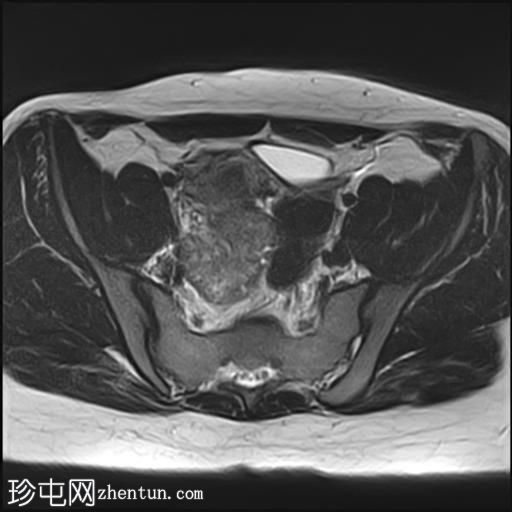

轴位

T2加权像

2个月前进行的MRI检查显示双侧卵巢肿块均有强化,右侧卵巢肿块未见扭转。

Krukenberg瘤患者单侧卵巢扭转的MRI特征。